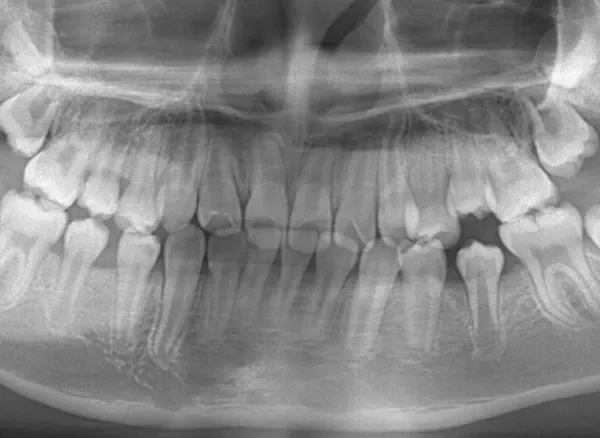

診断名 埋伏歯・反対咬合・叢生 装置名

レントゲンを撮ってみると犬歯の萌出方向がずれていました。

先ずは萌出スペースを確保してから開窓術を行い、犬歯を正しい方向へ誘導しました。